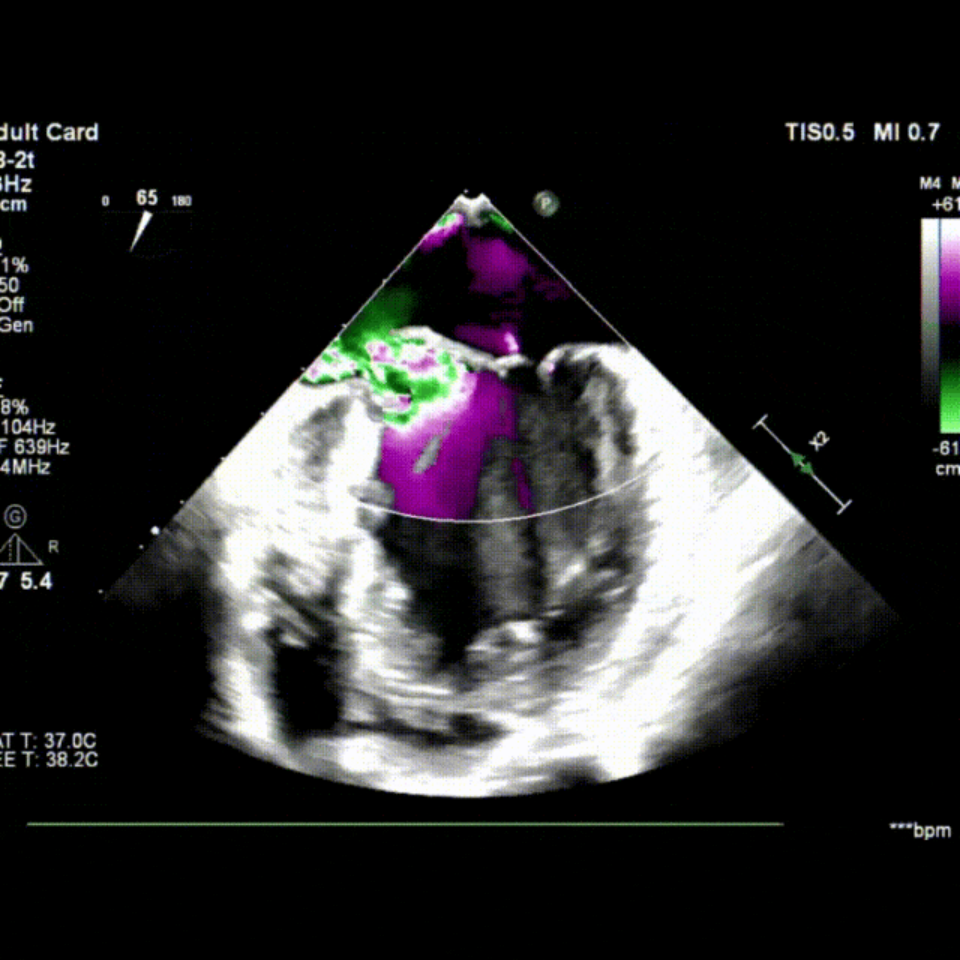

会议期间,张海波教授团队联合李伟教授完成了一例TA-TEER现场手术演示。患者为混合性二尖瓣反流(DMR+FMR),伴瓣环扩大、前瓣叶冗长、三区反流、后叶栓系及短小等复杂情况。术者在充分评估后选择置入双夹,手术获得圆满成功。现场专家就夹子型号选择、双夹放置位置及三区交界病变穿刺点等问题展开了深入讨论。

术前TEE影像

术中TEE影像